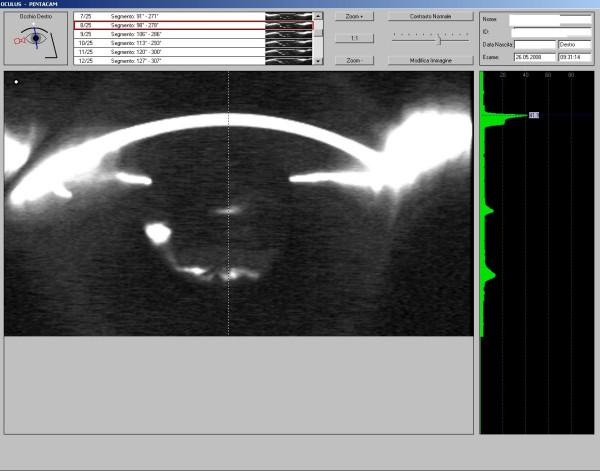

A 55-year-old man with myotonic dystrophy underwent phacoemulsification with IOL implantation in the right eye.3 months after surgery, the patient showed a decreased visual acuity and an intraocular pressure (IOP) of 30 mmHg. Slit lamp examination showed a dense fibrosis of the anterior capsule with capsulorexis' shrinkage. Gonioscopy showed a closed angle. After a YAG laser iridotomy no decrease in the IOP was detected; following surgical peeling of the anterior capsule, the slit lamp showed a distended capsular bag. A YAG laser posterior capsulotomy was performed, without decrease in the IOP. Myotonic patients need to be closely followed up after cataract surgery, because in case of CBS development a prompt posterior capsulotomy could avoid more severe complications.

一名患有强直性肌营养不良的55岁男性在右眼接受了白内障超声乳化吸除联合人工晶状体植入术。术后3个月,患者视力下降,眼压(IOP)为30 mmHg。裂隙灯检查显示前囊膜致密纤维化伴撕囊口收缩。前房角镜检查显示房角关闭。YAG激光虹膜切开术后眼压未降低;在前囊膜手术剥离后,裂隙灯显示囊袋扩张。进行了YAG激光后囊膜切开术,眼压仍未降低。强直性肌营养不良患者白内障手术后需要密切随访,因为一旦发生CBS,及时进行后囊膜切开术可避免更严重的并发症。